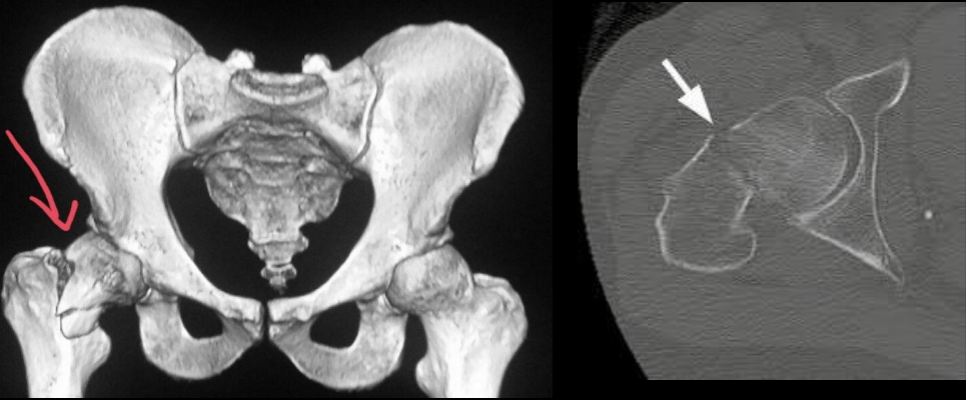

14

Q

A

Fx cuello femoral

15

Fx intertrocanterica

16